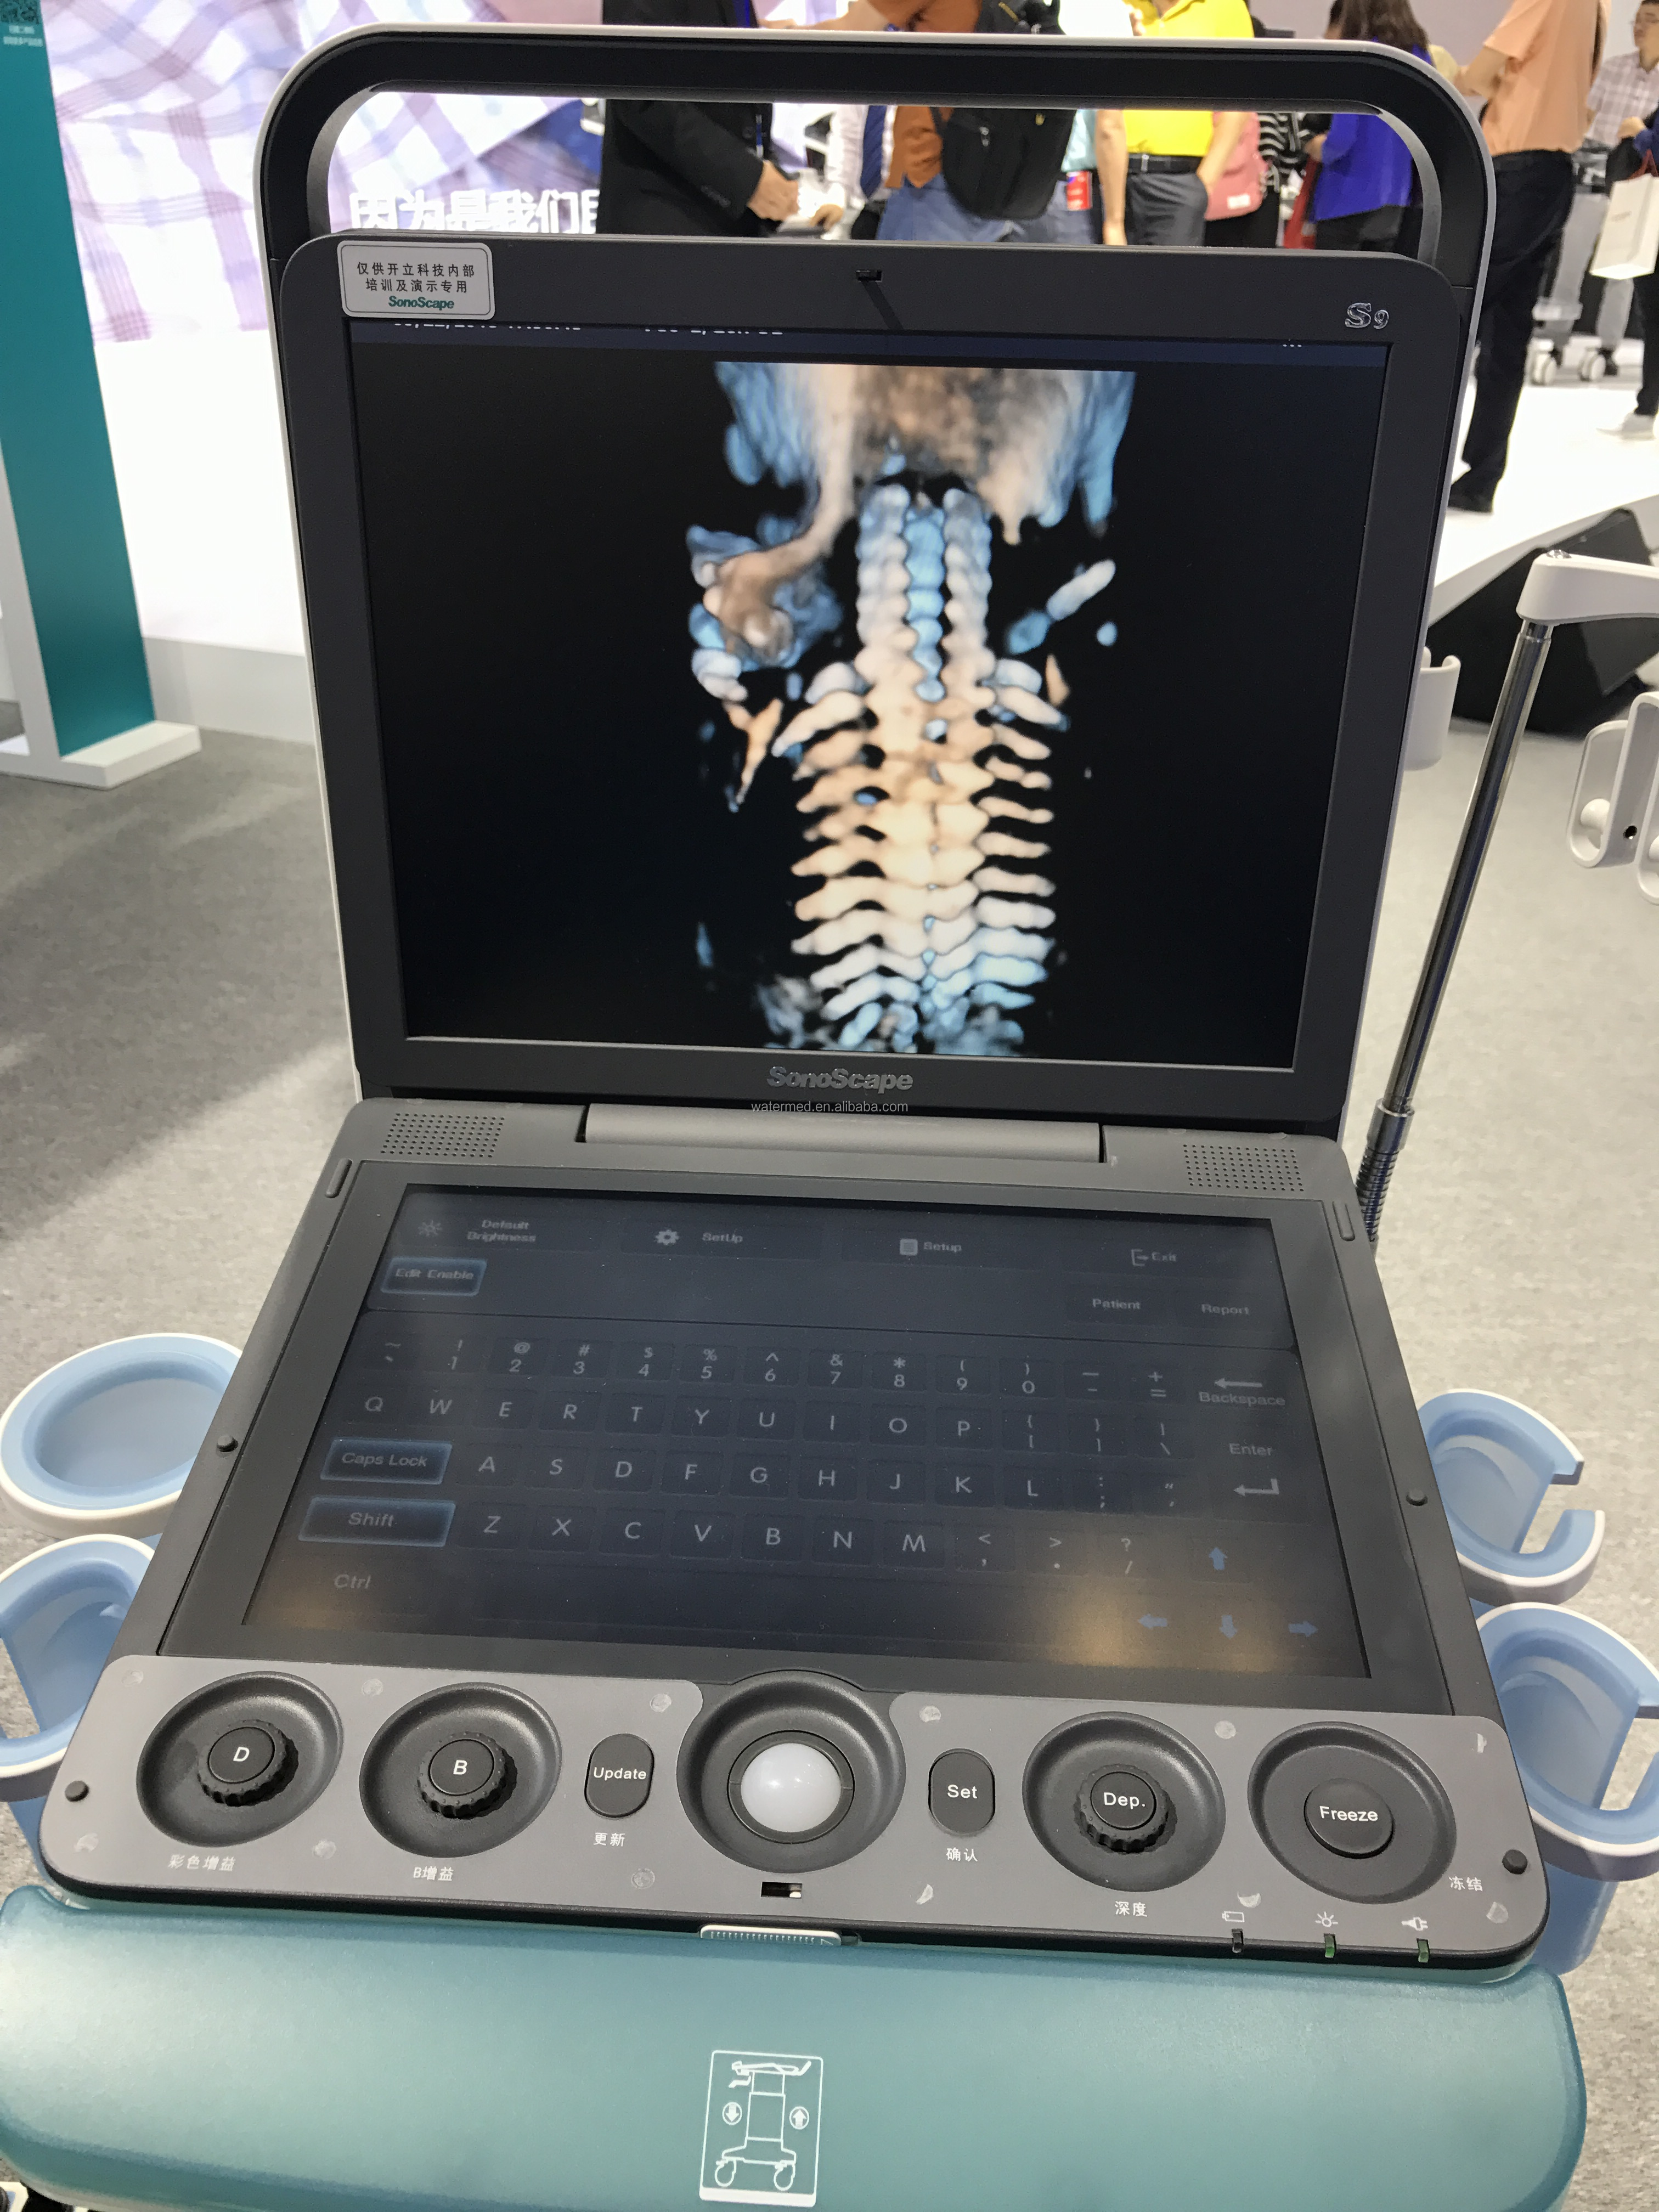

Real-time 3D (4D)

With the addition of physical channels and a new platform, the S9 delivers high-quality imaging and high frame rates to meet the new standard of the SonoScape S series. Thanks to the high frame rate and advanced technology, the S9's 4D imaging can realize the smooth movement of the fetus and provide comprehensive 4D acquisition, data rendering and post-processing functions.

With the addition of physical channels and a new platform, the S9 delivers high-quality imaging and high frame rates to meet the new standard of the SonoScape S series. Thanks to the high frame rate and advanced technology, the S9's 4D imaging can realize the smooth movement of the fetus and provide comprehensive 4D acquisition, data rendering and post-processing functions.